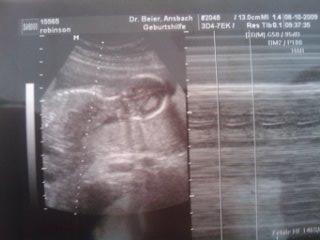

so heute wars bei mir auch wieder soweit und ich hatte VU..mein mann war heute auch mit dabei was mich sehr gefreut hat.. klappt bei ihm meistens nicht wegen job..tja und dann hatten wir heute unser outing!! er hat ganz lange rumgeschallt..erst den kopf gemessen dann den oberschenkelknochen und dann den bauch durchmesser usw.. ich hab mir nur gedacht "mensch schall zwischen die beine!!!" und dann hat er endlich geguckt was es wird..hat extra lang geschallt hat das baby etwas geschuettelt damit es sich mal bequemt die beine auseinander zumachen..hat dann auch in zeitlupe geschallt und immer mal wieder festgehalten und dann wars raus wir bekommen ein MAEDCHEN!! ich hab mich so gefreut! ich wollte undbedingt ein maedchen da wir ja schon nen jungen haben ich bin gerade sooo uebergluecklich!! hab am 29.10 nochmal nen termin.. hoffentlich bleibts beim maedchen hier mal die bilder und DAS beweisfoto.. LG manu

Bild zu zurueck vom FA + OUTING!!!! - Forum für März - Mamis

und hier noch das beweisbild...das is von unten also popo geschallt und man kann die zwei schamlippen sehen wenn man genauer hinguckt!